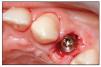

Para colocar los implantes en los lugares de extracción, se usaron puntas de osteotomía. La punta piloto se colocó frente a la pared palatina para efectuar una muesca en el alveolo en su tercio apical. La angulación de la punta tuvo en cuenta una desviación palatina de unos cinco grados desde el eje del diente (figura 4a). Con la activación de la punta piloto, se creó la muesca con la angulación correcta sin que se produjera el deslizamiento del instrumento. No se requirió ningún esfuerzo para mantener la angulación seleccionada en el punto escogido. Con la misma punta la muesca se extendió a una profundidad del canal de 3-5 mm, apical al vértice del alveolo. El ensanchamiento de la osteotomía se efectuó con puntas de diámetro cada vez mayor (figura 4b). Más allá del alveolo de extracción, la osteotomía fue de forma cónica, similar a la obtenida con los osteotomos de Summers.

Figura 4 Preparación del lugar de osteotomía y colocación del implante.

Figura 4c (derecha) El implante se colocó en el alveolo de extracción. Obsérvese el espacio izquierdo entre el implante y la pared cortical (> 2 mm).